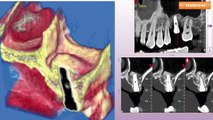

Roma, 1 mar. (askanews) - Fondazione SIRM si affida alla tecnologia Canon, come il Sistema EOS VR e la piattaforma ecografica Aplio i-series Prism Edition, per dare vita a una nuova didattica basata sulla realtà virtualeIl Sistema EOS VR di Canon rappresenta un ulteriore progresso tecnologico, hardware e software, che nasce dalla consolidata capacità dell'azienda di sviluppare continuamente soluzioni di imaging sempre all'avanguardia sia in ambito fotografico sia in quello della diagnostica per immagini. Con l'iniziativa messa a punto in collaborazione con Canon Medical System e con Fondazione SIRM, la tecnologia VR e le soluzioni Canon permettono di offrire un metodo innovativo per favorire l'apprendimento in campo medico.Un potente strumento che, grazie alle nuove tecnologie VR, rende più appetibile l'accesso a informazioni di difficile comprensione. La didattica e le modalità di apprendimento si evolvono rapidamente in un mondo sempre più connesso e digitale. Per questo, Canon Medical ha deciso inoltre di mettere insieme due tecnologie d'eccellenza: la piattaforma ecografica Aplio i-series Prism Edition e il Sistema EOS VR.Per Simone Cavalcoli, Pro Sector & Industries Business Development Manager di Canon Italia, attraverso questa tecnologia immersiva si creano esperienze uniche e coinvolgenti che possono avere tantissime modalità di impiego, vedi la collaborazione con la Fondazione Sirm. Con Paolo Tedeschi, Direttore Comunicazione di Canon Italia, che ricorda come Canon investa ogni anno l'8% del fatturato in ricerca e sviluppo ed è grazie a questo impegno che oggi è in grado di presentare un intero ecosistema di soluzioni e servizi che risponde alle esigenze dei professionisti più affermati in ogni ambito e settore merceologico.